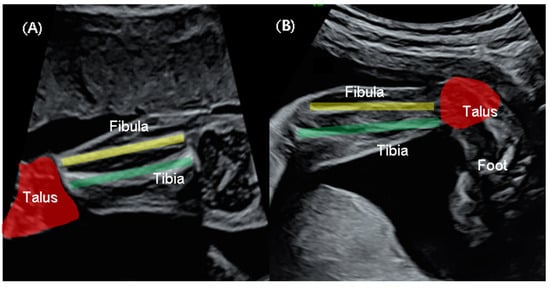

2.3. Sonographic Measurements